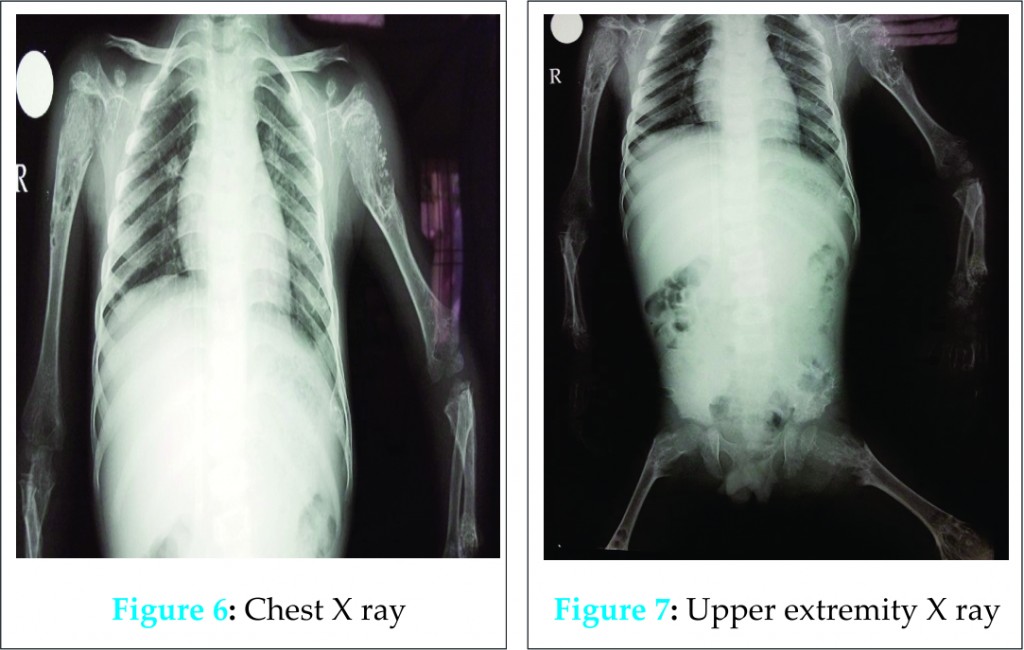

A five years male child presented to the paediatric OPD with complaints of recurrent upper respiratory tract infection. On examination he had swelling of the joints for which the child was referred to our OPD. Examination revealed that the swelling was non-tender, bony hard and did not show any effusion. Thorough examination with proper history taking was done which revealed that the child was born of a 3rd degree consanguineous marriage at home after 38 weeks of gestation from the third pregnancy of a healthy 26-year-old mother and 30 yrs old father. The mother was under routine prenatal follow-up during pregnancy. There was no history of intake of toxic drug or any chronic medications. The mother had two deliveries, the first two children being normal. Birth Weight of this child was 2.4 kgs. Currently at 5 yrs of age, weight is 10.2 kgs, Length of Upper extremities (41cms) and that of lower extremities (36.5 cms), height is 81 cms, head circumference is 47 cms, chest circumference is 49 cms. The patient had history of upper respiratory tract infection frequently (once a month or once in 2 months). Clinically, the child had congenital cataract in left eye and early cataract changes in Right eye (Fig 1). Facial features showed prominent forehead, widely set eyes and a sunken face (Fig 2). The patient can speak sentence, can run, can dress and undress himself. At 1.5 yrs of age he started sitting without support and speaking bisyllables. The child was walking with limp. All Milestones were achieved till date. Weight by age and height by age was less than 3rd percentile (Fig 4). Normal weight should have been around 18 kgs (weight is 10.2 kgs) and normal height around 115 cms (height is 81cms). The radiological findings of the patient were compatible with CDP with punctate calcifications in the epiphyses and metaphyseal dysplasia (Fig 5,6,7). Blood investigations revealed Alkaline phosphatase – 160, serum Ca+ – 9.2, Sr. phosphorous – 5, ESR – 130. RCDP was diagnosed based on clinical and radiological criteria.